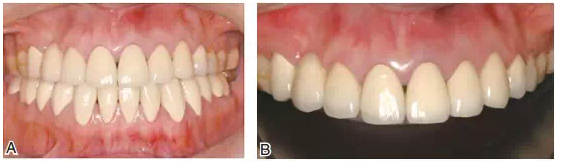

圖18修復(fù)完成后的上下頜咬合面觀

圖19患者修復(fù)完成后的正面像及牙合曲線